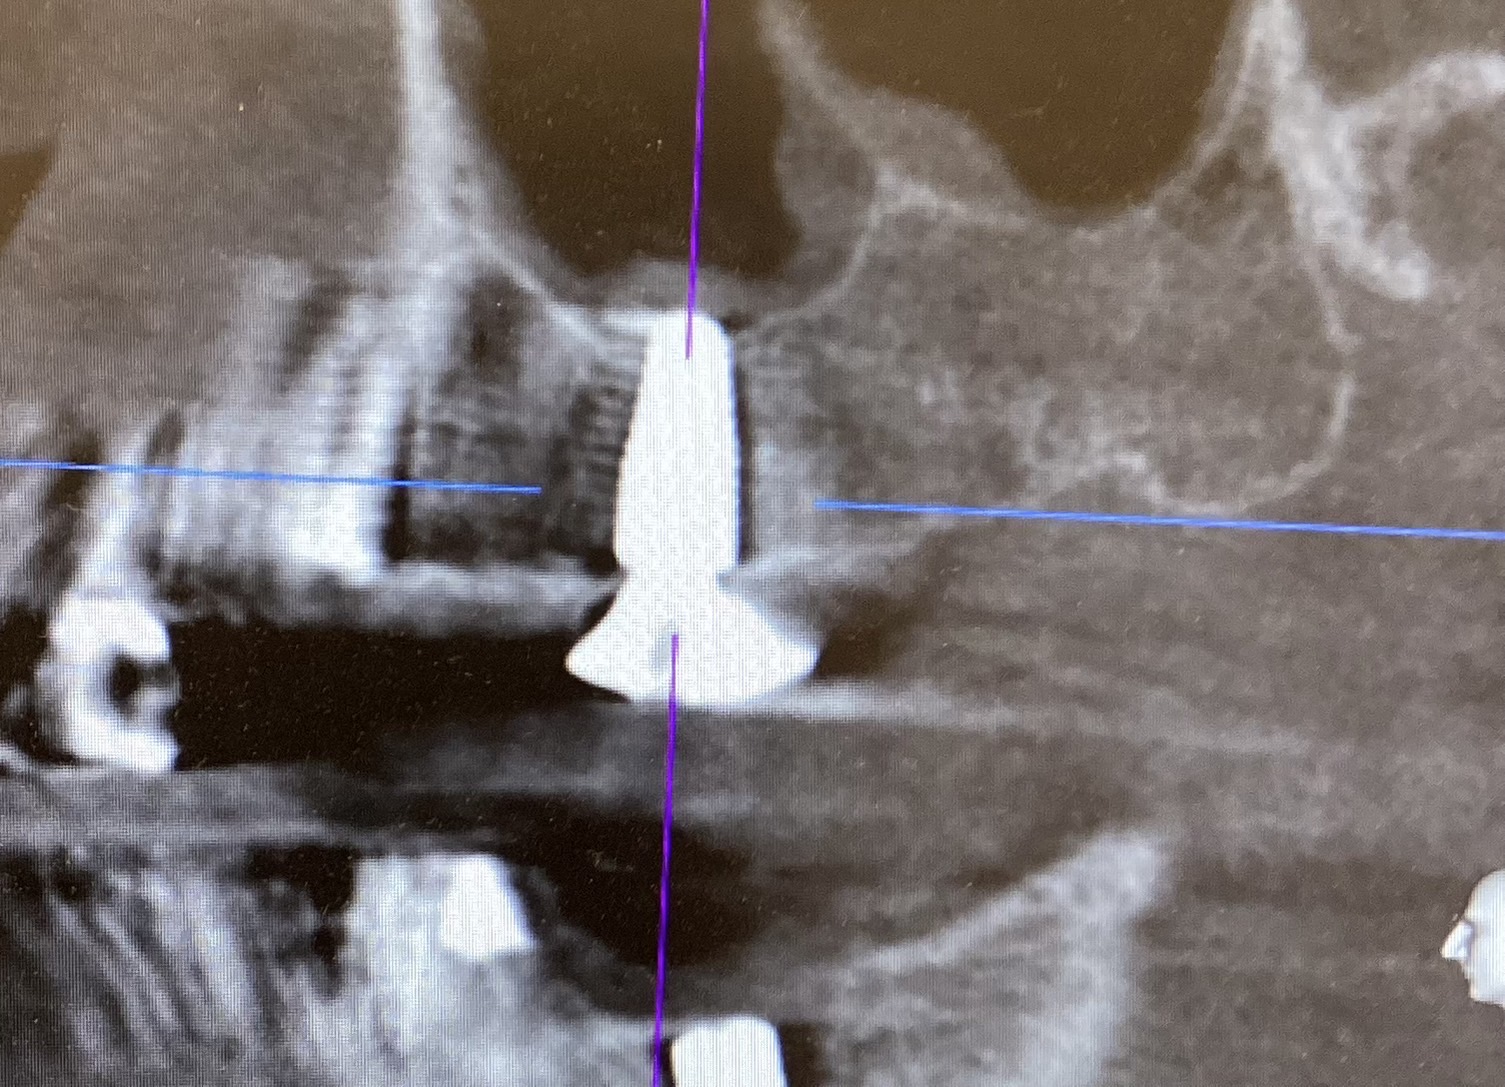

• 前歯のインプラント抜歯即時埋入

前歯のインプラント抜歯即時埋入

• インプラント抜歯即時埋入

インプラント抜歯即時埋入